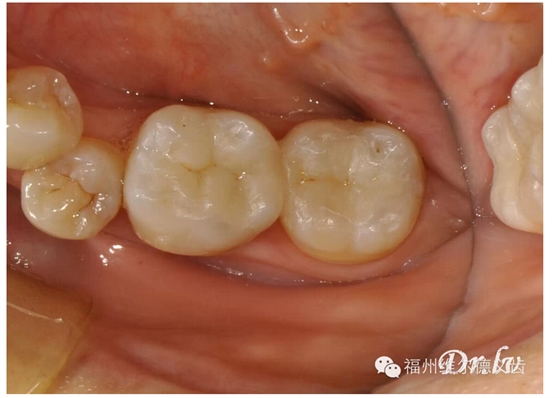

這次機會又沒抓住的話,牙的齲壞開始深了,涉及的牙面多了,這時候單純補牙不行了,需要做嵌體,才能把壞的部分修補好,嵌體要幾百到兩三千不等,有點貴了。

這時候又沒處理,齲齒向深層的神經(jīng)侵襲,表現(xiàn)為牙痛的不行,這時候的治療叫根管治療,后牙的現(xiàn)代根管治療技術(shù)通常要兩千元左右,而且這不算完,大多數(shù)牙齒在根管治療之后需要做一個牙冠保護起來,就是常說的烤瓷牙了,這烤瓷牙便宜的要幾百元,貴的要七八千元,這一套都下來少則兩三千,多則上萬,這時候普通人承受起來普遍比較吃力了。